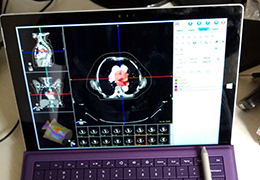

Parametric and non-parametric statistical maps may be superimposed both on the original functional scans as well as onto T1-weighted 2D or 3D anatomical reference scans. Time courses of selected regions-of-interest (ROIs) are available both in 2D and 3D representations. Statistical maps may be computed either in the 2D or 3D representation since structural as well as functional 4D data (space x time) are transformed into Talairach space. This allows you to compare activated brain regions across different experiments and across different subjects

Segmentation of tissue (e.g., isolating the brain, differentiating gray and white matter) is performed using region-growing methods, filter operations as well as the application of 3D templates. Using the mouse it is very easy to explore a 3D volume with superimposed pseudocolor-coded statistical maps in a four-window representation showing a sagittal, coronal, transversal and oblique section. Based on a (segmented) 3D data set a three-dimensional reconstruction of the subjects' head and brain can be calculated and displayed from any specified viewpoint using volume or surface rendering.